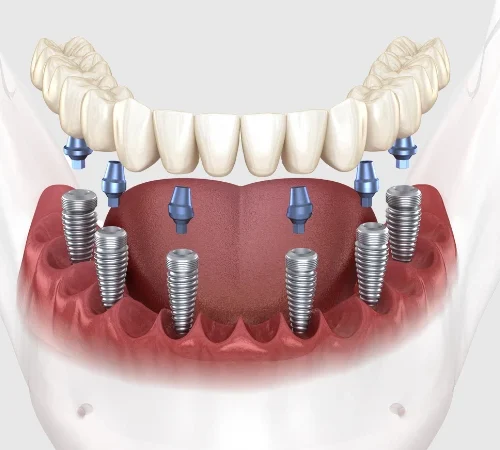

All on Four ve All on Six İmplant

Tamamen dişsiz veya kalan dişleri çekilmesi gereken hastalar için tek bir operasyonda ve tek bir protez ile sabit dişlere kavuşma imkanı sunan yenilikçi çözümlerdir. Hızlı iyileşme ve yüksek konfor sunar.

3) All-on-Four / All-on-Six bana uygun mu?

Tam dişsizlikte tek aşamada sabit proteze geçiş için iyi seçeneklerdir. Kemik hacmi, sistemik durum, sigara alışkanlığı ve hijyen motivasyonu değerlendirilir. Geçici–kalıcı protez zamanlaması hastaya özelleştirilir.